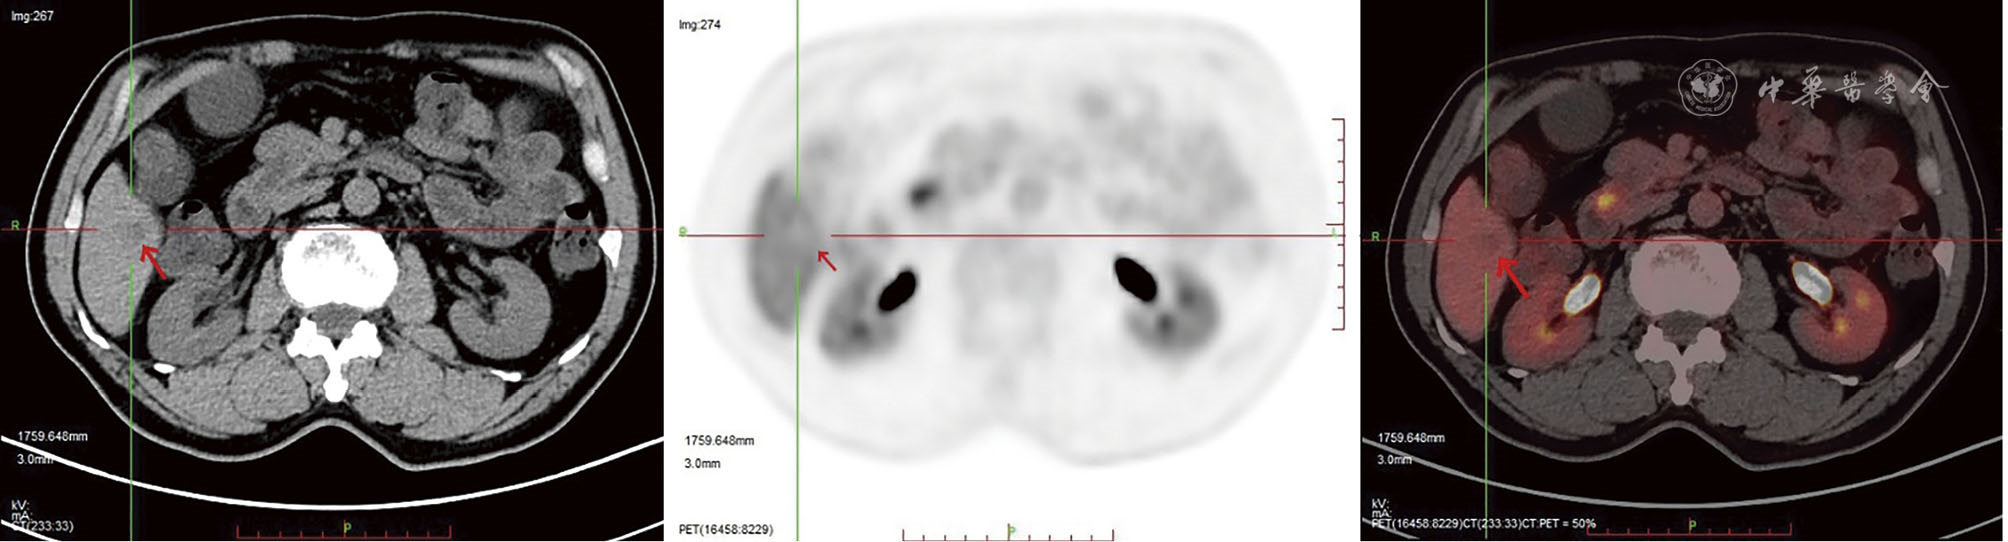

In this report, a 63-year-old male patient was admitted due to "dull pain in the right upper abdomen for 2 months". Imaging and pathological examination confirmed the diagnosis of synchronous hepatocellular carcinoma (CNLC Ⅰa stage) and duodenal papillary carcinoma (moderately-poorly differentiated adenocarcinoma complicated with signet ring cell carcinoma). The patient had a history of chronic hepatitis B. After Multidisciplinary team (MDT) consultation, laparoscopic local resection of segment 5 of the liver combined with pancreatoduodenectomy were performed to achieve R0 resection. Liver metastasis occurred 2 months after operation, and it was completely relieved after TACE, tirelizumab immunotherapy and FOLFOX4 chemotherapy. Postoperative survival time has exceeded 16 months. This case of synchronous double primary carcinoma of the liver and duodenal papilla is extremely rare, and it is likely to miss the diagnosis in clinical practice, suggesting that after the diagnosis of one type of malignant tumor, comprehensive evaluation is still needed to exclude other primary lesions. PET-CT shows important value in the early identification of such multiple primary cancers. Through multi-mode strategy of individualized comprehensive treatment and whole-course management, this patient achieved favorable tumor control effect, providing reference for clinical diagnosis and treatment of such rare cases.